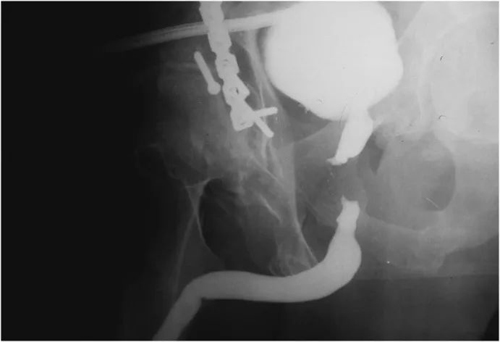

骨盆骨折导致的创伤性尿道狭窄尿道造影图像

导致球膜部尿道狭窄最常见的原因是创伤性骨盆骨折。当骨盆骨性结构发生骨折或移位时,通常会挤压脆弱的球、膜部尿道,从而使尿道管腔缩小,远期则形成尿道瘢痕。这些患者常常在急诊抢救室试行导尿时,会发现尿管置入困难,同时合并尿道出血,通常需要泌尿外科专科医师行膀胱造瘘术,来解决伤后即时排尿问题。由于病因相对明确,远期则可以根据尿道狭窄的情况决定尿道修复的手术方式。